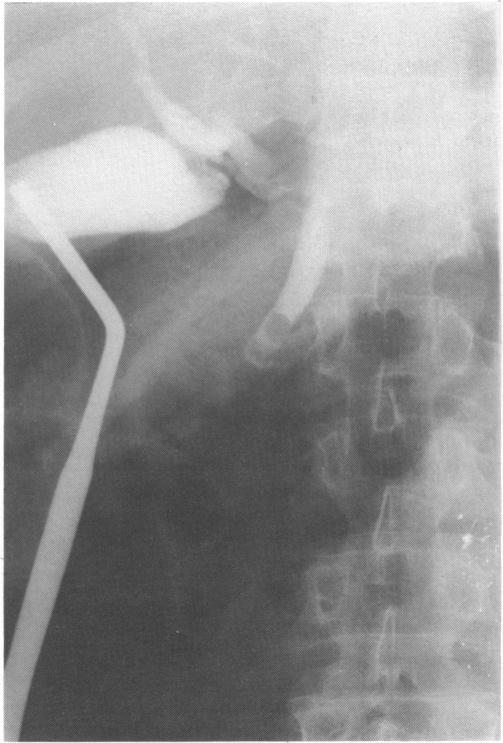

Transcholecystic operative cholangiography: an alternative technique.

Percutaneous transcholecystic cholangiography: experimental study.

Intraoperative cholangiography for laparoscopic cholecystectomy.

CHOLANGIOGRAPHY: VISUALIZATION OF THE GALLBLADDER AND BILE DUCTS DURING AND AFTER OPERATION.

Cystic-duct cannula and cannula-holding clamp for operative cholangiography.